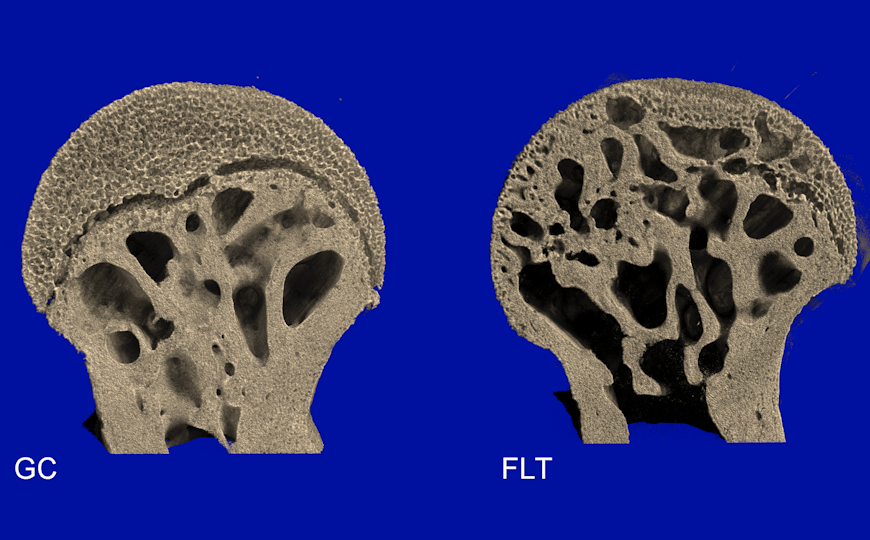

Костная и хрящевая ткань в головке бедренной кости мыши, побывавшей на околоземной орбите (FLT), отличается от оставшегося на Земле контроля (GC). Хрящевая ткань подвергается преждевременному вторичному окостенению в условиях микрогравитации.

Особое внимание авторы статьи уделили бедренной кости, которая в теле мыши выполняет основную несущую функцию. Они обнаружили, что процентный объем костной ткани в головке бедренной кости значительно уменьшился после пребывания в космосе. Другие признаки, включавшие плотность соединения и характеристики трабекул (перекладин, формирующих структуру губчатого вещества кости), также указали на выраженную атрофию костной ткани.

Другое важное наблюдение, сделанное авторами, касалось вторичного окостенения. Микрогравитация ускорила этот процесс в хряще, покрывающем головку бедренной кости, и окостенение было сопряжено с потерей активности хондроцитов.